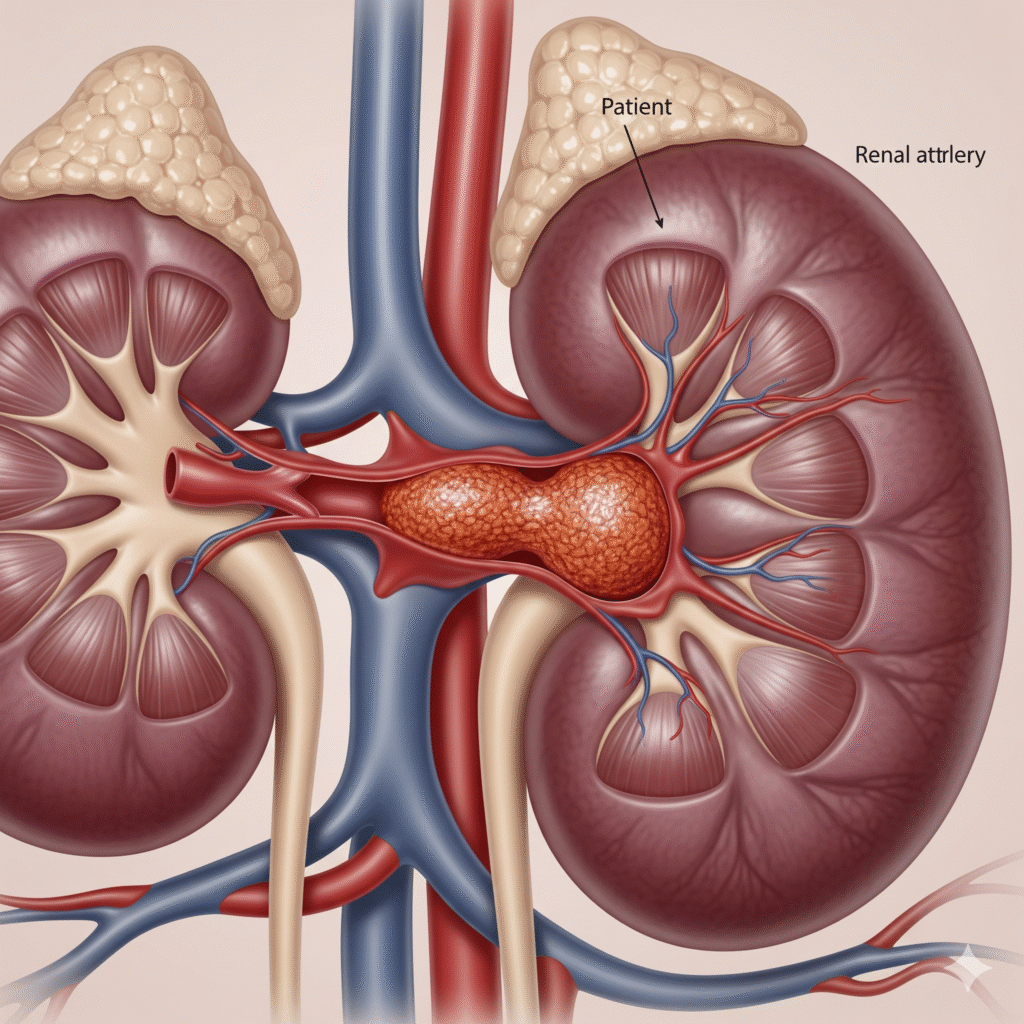

A trombose da veia renal é uma doença caracterizada pela formação de um coágulo sanguíneo (trombo) dentro da veia que drena o sangue do rim. Esse bloqueio prejudica a circulação sanguínea renal, podendo levar a complicações graves, como perda da função do rim afetado, embolia pulmonar e insuficiência renal aguda.

O que é a trombose de veia renal?

Cada rim possui uma veia que leva o sangue “filtrado” de volta para a circulação. Quando ocorre a obstrução dessa veia por um coágulo, o fluxo é interrompido ou reduzido, comprometendo o funcionamento do rim.

Pode ser aguda, com sintomas súbitos, ou crônica, de evolução mais lenta e silenciosa.